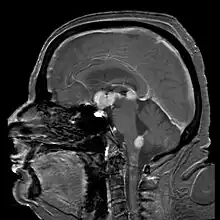

| Brain magnetic resonance imaging showing primary central nervous system B-cell non-Hodgkin lymphoma of the sella turcica and hypothalamus, continuing to the tectum (intensely white areas in the middle). | |

MRI or contrast enhanced CT classically shows multiple ring-enhancing lesions in the deep white matter. The major differential diagnosis (based on imaging) is cerebral toxoplasmosis, which is also prevalent in AIDS patients and also presents with a ring-enhanced lesion, although toxoplasmosis generally presents with more lesions and the contrast enhancement is typically more pronounced. Imaging techniques cannot distinguish the two conditions with certainty, and cannot exclude other diagnoses. Thus, patients undergo a brain biopsy or vitreous biopsy, if there is intraocular involvement.[10]